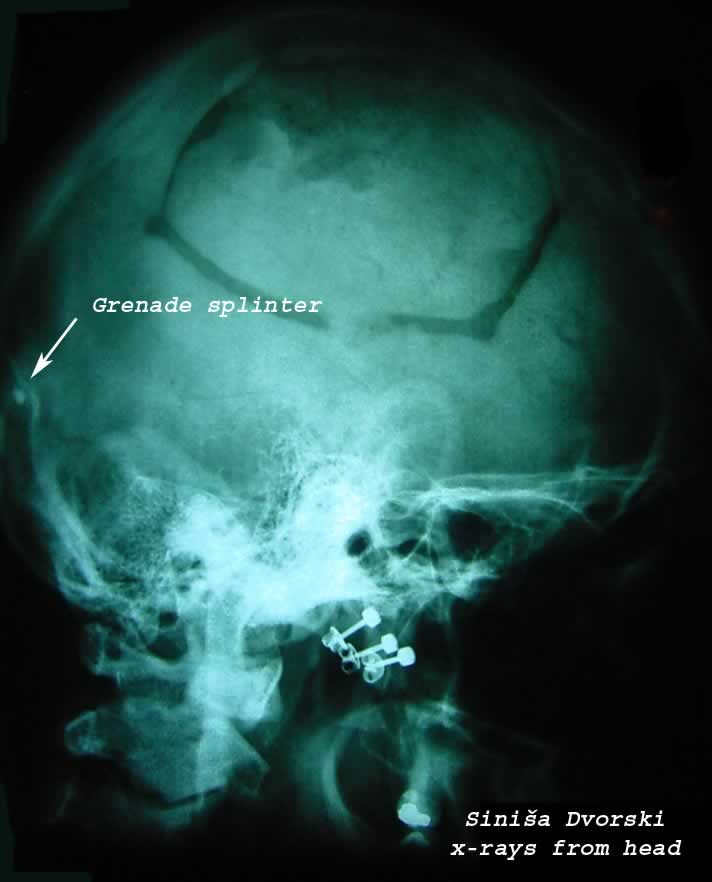

The second time, 08/28/1991, I was wounded from a peace of a grenade that came in to my head. This time I was bleeding like I was standing in the rain of blood. My blood was flowing down from my head in a strong stream. At the moment I was hit from the solid metal, witch came from a grenade that a tank has fired on my fighting position; I was flying away from the blast of the explosion several meters. When I stand up, I was looking for my rifle and I saw my left arm. He was not responding on my commands. I was paralyzed on the left side of the body, but I didn’t give a shit. Looking around me I saw 3 soldiers lying on the ground. They where also hit from the grenade and they where also bleeding, so I gave the command to get the jeeps and transport the wounded soldiers into the nearest hospital and my driver helped them to get them into the car. My deputy took the first aid kit and stopped the bleeding on my head. After 2 minutes we drove to the hospital. I had never seen the hospital before. After 3 minutes in the jeep I fainted. I woke up in the hospital in Zagreb. The next day, the first thing I asked: “Where the fuck is my rifle?!”

Today I am still alive and kicking. The solid metal peaces in my ribs and in my head are still inside me and I am carrying them with proud. Sometime when I fly with the plane, the metal detector rings on the airport, but I didn’t mind it. It remembers me on the days that I fought for Croatia. After only 2 weeks hospital, I escaped with a motor bicycle and returned to my team “ZEBRA”.